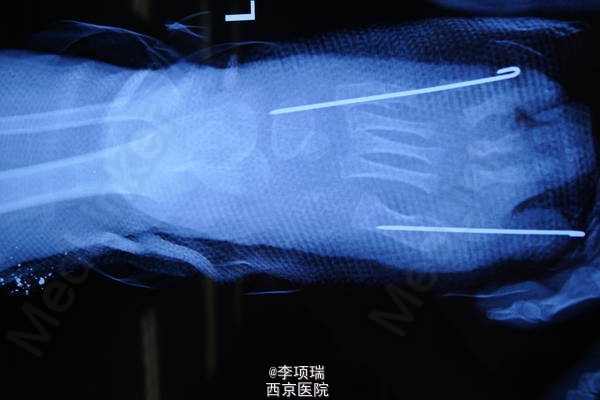

患儿,女,2岁,左足7个趾头伴并趾。

左足7个趾头伴并趾

第二趾切除,第一趾复位后跖骨腓侧契形截骨克氏针固定,第7趾切除,第6趾 跖骨契形截骨克氏针固定。